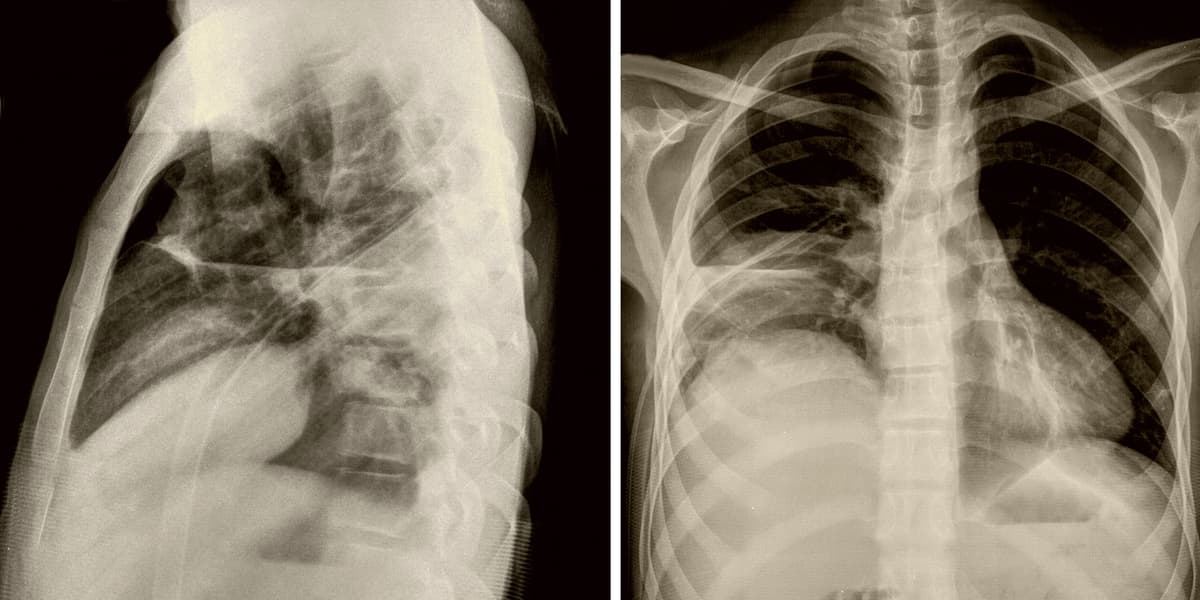

Atelektazi tanısı genellikle akciğer filmi ile konulur. Gerekli görülen durumlarda bronkoskopi de yapılabilir. Ayrıca, altta yatan nedenin tespit edilmesi için doktorlar farklı testler isteyebilirler.